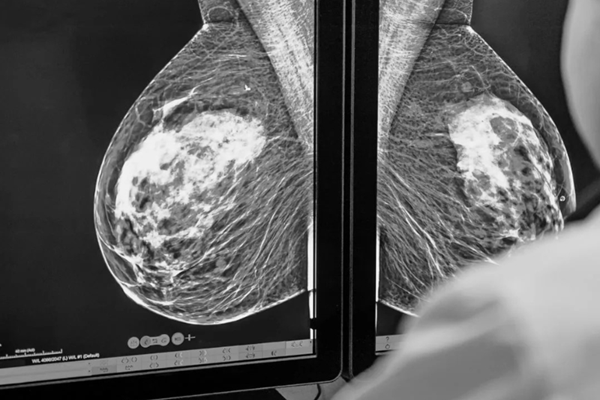

Chụp nhũ ảnh là gì? Những đối tượng nên thực hiện chụp nhũ ảnh

Ung thư vú là một trong những bệnh lý ác tính phổ biến hàng đầu ở phụ nữ. Việc ...